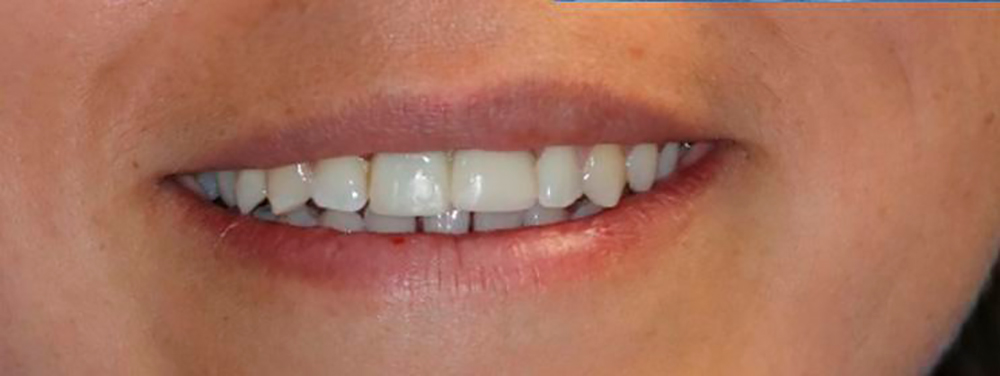

Final Stage Of The Restoration